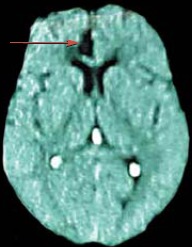

Brain Defect

Smegenų skenavimas parodo defektą, kuris sukelia psichikos funkcijų sutrikimą. Sužeidimas juostos vingyje (rodo rodyklė) sukelia išsigalvojimų kūrimą.